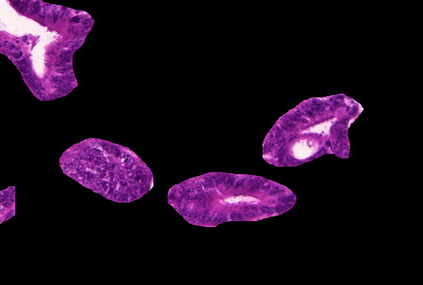

Weakly-supervised learning (WSL) has recently triggered substantial interest as it mitigates the lack of pixel-wise annotations. Given global image labels, WSL methods yield pixel-level predictions (segmentations), which enable to interpret class predictions. Despite their recent success, mostly with natural images, such methods can face important challenges when the foreground and background regions have similar visual cues, yielding high false-positive rates in segmentations, as is the case in challenging histology images. WSL training is commonly driven by standard classification losses, which implicitly maximize model confidence, and locate the discriminative regions linked to classification decisions. Therefore, they lack mechanisms for modeling explicitly non-discriminative regions and reducing false-positive rates. We propose novel regularization terms, which enable the model to seek both non-discriminative and discriminative regions, while discouraging unbalanced segmentations. We introduce high uncertainty as a criterion to localize non-discriminative regions that do not affect classifier decision, and describe it with original Kullback-Leibler (KL) divergence losses evaluating the deviation of posterior predictions from the uniform distribution. Our KL terms encourage high uncertainty of the model when the latter inputs the latent non-discriminative regions. Our loss integrates: (i) a cross-entropy seeking a foreground, where model confidence about class prediction is high; (ii) a KL regularizer seeking a background, where model uncertainty is high; and (iii) log-barrier terms discouraging unbalanced segmentations. Comprehensive experiments and ablation studies over the public GlaS colon cancer data and a Camelyon16 patch-based benchmark for breast cancer show substantial improvements over state-of-the-art WSL methods, and confirm the effect of our new regularizers.